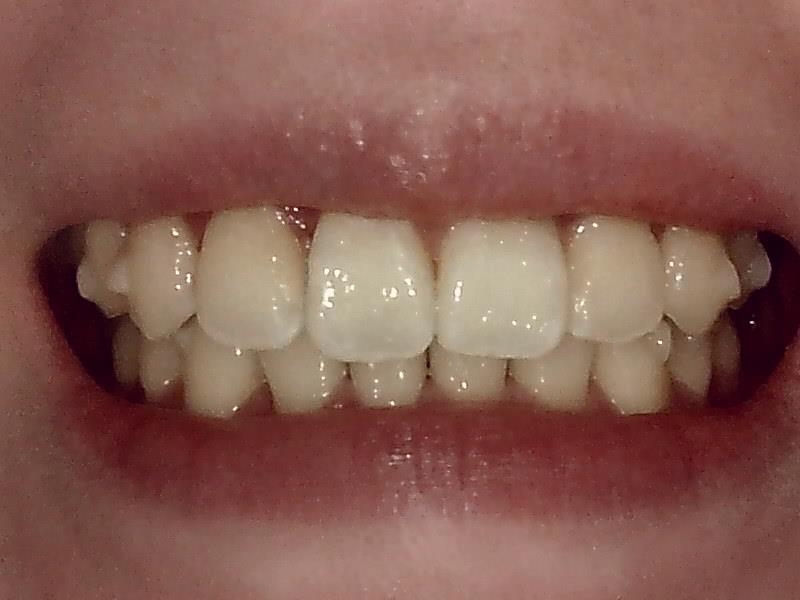

部位:左下8番骨性完全埋伏歯

切開 歯肉剝離

抜歯窩

歯肉を切開し、歯が見えるようにして、

周辺の骨を削らないように親知らずを分割し抜きやすくしていきます。

この抜歯法により術後の腫れ痛みが大幅に軽減されます。

傷口は最小限に、骨は極力削らずに行います。

骨が歯を覆っているケース以外は骨を削ることはありません。

親知らずのみにアプローチし歯を分割し最小限の傷口で取り出します。

縫合

抜歯後、経過良好です。